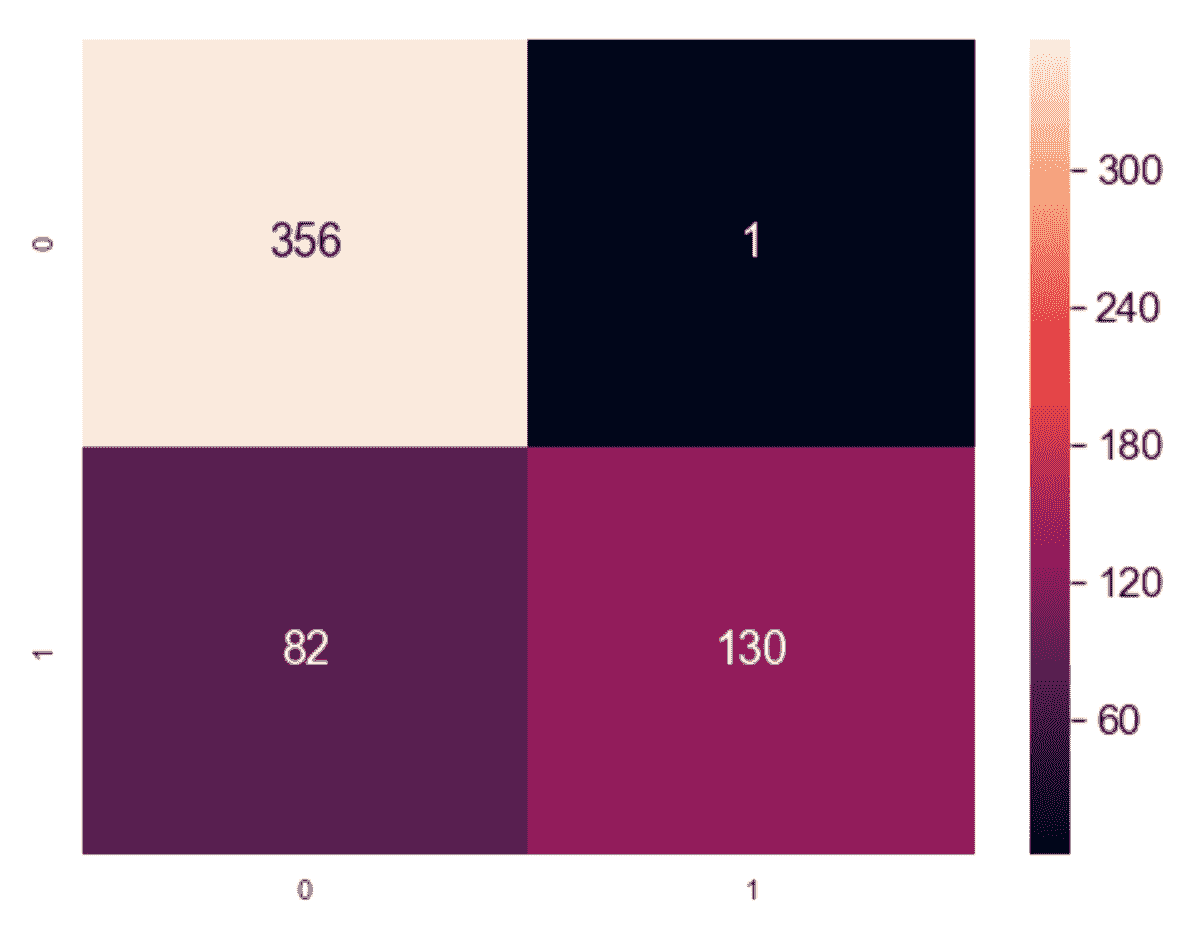

权变矩阵

一个非常简单而强大的工具,可以在已知真实情况时显示聚类算法的表现,它是权变矩阵C[m]。 如果存在m类,则C[m] ∈ ℜ^(m×m)和每个元素C[m](i, j)代表已分配给群集j的Y[true] = i的样本数。 因此,一个完美的权变矩阵是对角线的,而所有其他单元格中元素的存在则表明了聚类误差。

在我们的案例中,我们获得以下信息:

from sklearn.metrics.cluster import contingency_matrix

上一个代码片段的输出可以显示为热图(变量cm是2×2矩阵):

权变矩阵的图形表示

该结果表明,几乎所有良性样本均已正确聚类,而适度百分比的恶性样本已被错误地分配给第一个聚类。 我们已经使用其他度量进行了确认,但是类似于分类任务中的混淆矩阵,列联矩阵可以立即可视化最难分离的类别,从而帮助数据科学家寻找更有效的解决方案。